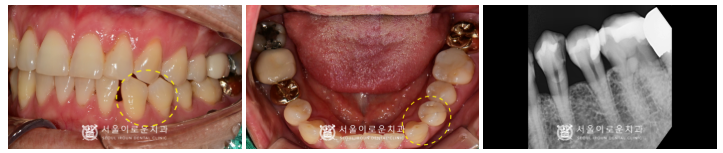

파노라마 뿐만 아니라

치근단 사진, 3D-CT를 통해

구강 내 해부학적 구조물과

상악동과의 거리 등을 파악하고,

임플란트의 식립 위치 및 방향 등

여러가지 사항을 고려하여

발치 후 수술을 진행하였답니다.

잔존 뼈와 상악동과의 수직적인 높이가

3mm가 채 되지 않아

상악동 거상술 중 ‘측방 접근법’을 활용하여

수술을 진행하였습니다.

술 후 파노라마와 3D-CT를 통해

상악동 거상술을 동반한 임플란트가

안정적으로 식립된 것을

체크하였답니다.